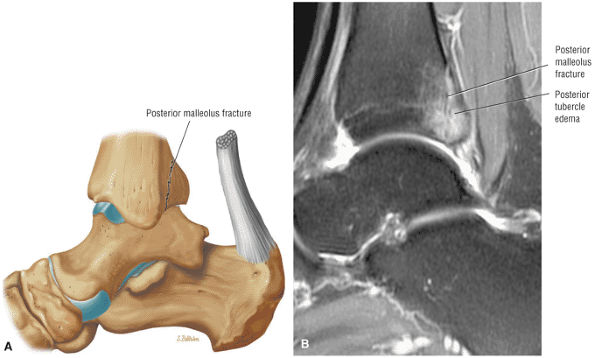

![]() |

|

FIGURE 5.28 Tibiotalar Joint.

FIGURE 5.29 Impingement.